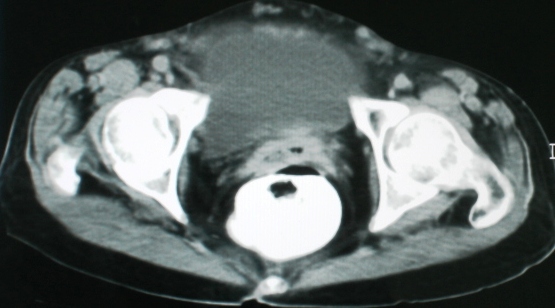

以下是引用zsl6918在2008-11-4 19:14:00的发言:[br]多发转移性改变,子宫改变不除外为原发灶